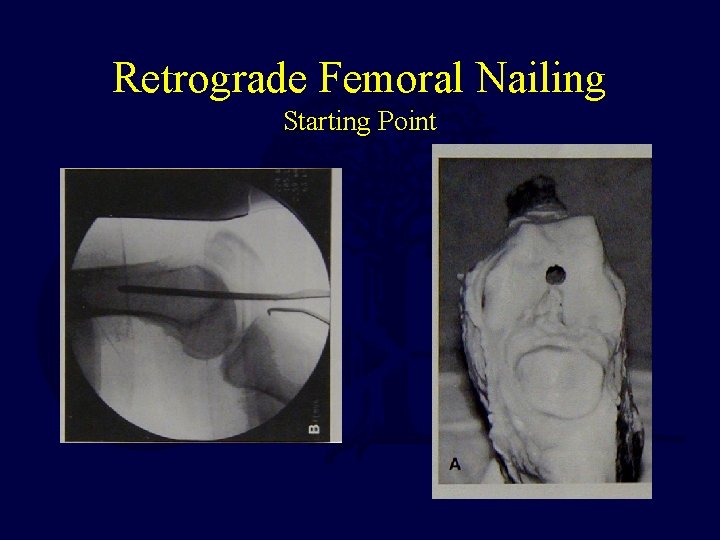

Femur Fracture Technique • Retrograde Intramedullary Nailing – Supine - flex the knee 50° to allow access to Blumensaat’s line Percutaneous with fluoro OR Limited open technique

Retrograde Femoral Nailing Starting Point